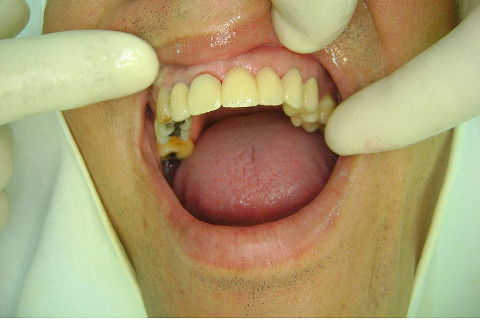

Paciente apareceu em meu consultório em dezembro/2013 para resolver problema de insatisfação com ponte fixa provisória anterior, realizada há 9 anos atrás (2004)...pretendia realizar somente a reabilitação em maxila/anterior, não contava com outros problemas com maior gravidade na sua boca, o máximo que citou foi a indicação para a exodontia do 16...

O meu planejamento já está decidido junto com o paciente somente trabalhos provisórios sobre implantes mesmo na região anterior, até que ele resolva pela reabilitação total. "Carro com pneu careca é para trocar os 4, não adianta colocar só 2..."